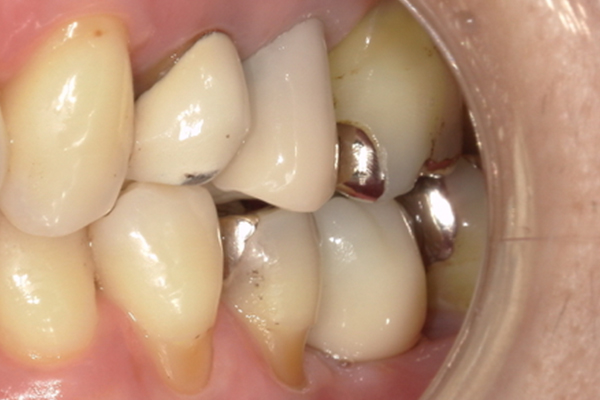

| 主訴 | 歯が痛い |

|---|---|

| 治療内容 | 右上奥歯に対するインプラント治療 (今後右下に対してもインプラント治療を予定) |

| 治療期間 | 6ヶ月 |

| 治療費 | 44万5千円 |

| 治療 リスク | インプラントを埋入したあと3ヶ月程度待ち時間が必要。 その期間は仮歯を使用していただきます。 |